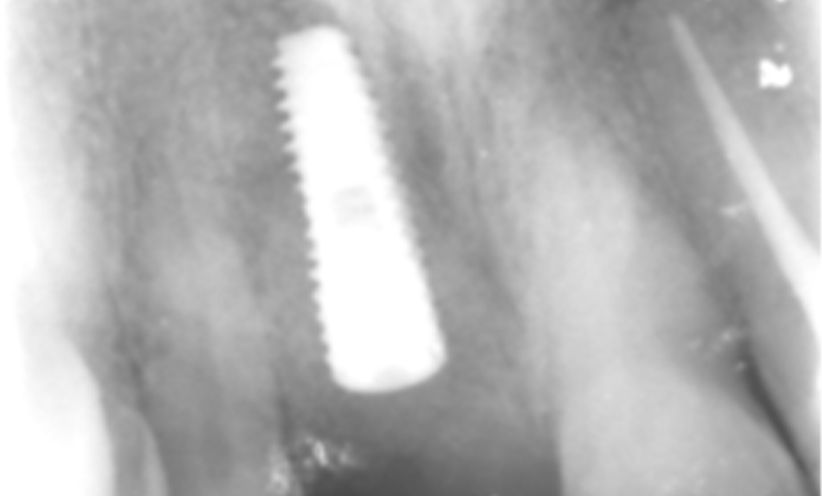

Case 5